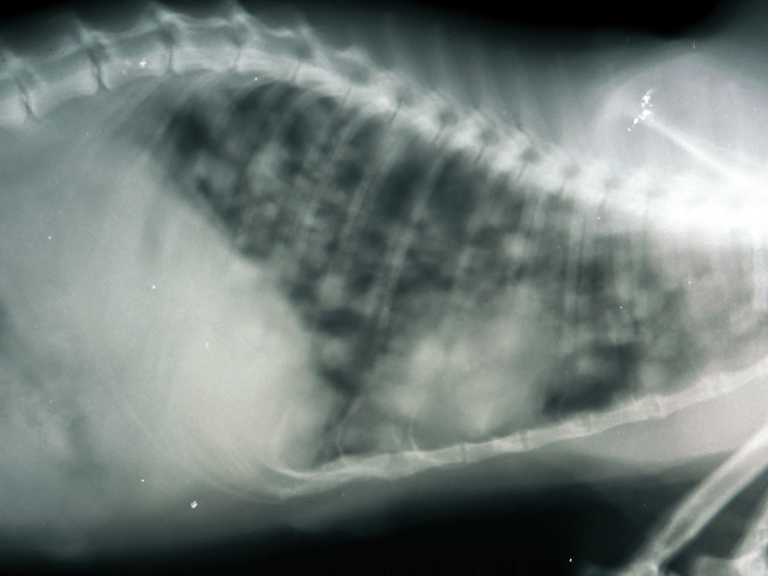

CARCINOMA PULMONAR EN GATO Veterinario Traumatólogo